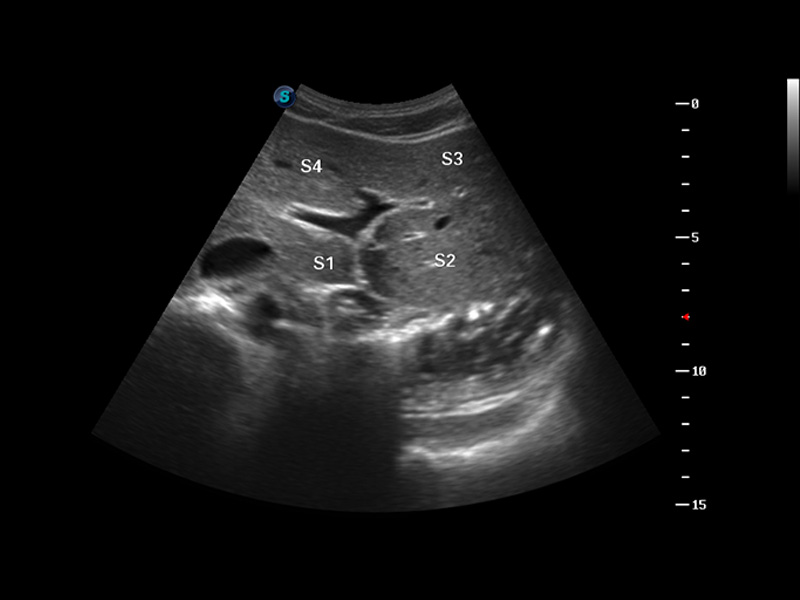

S8 EXP便攜式彩色多普勒超聲診斷儀是開立醫(yī)療研發(fā)的高端全身應(yīng)用型便攜彩超。高通道的VIS平臺融合可視化(Visual)、智能化(Intelligent)和人性化(Smart)的特點,配以開立醫(yī)療自主研發(fā)生產(chǎn)的探頭大家族,使您能夠快速、準(zhǔn)確的獲得病人信息,提高工作效率的同時減輕疲勞。

成像技術(shù)

多波束形成器

μ-Scan微米成像

諧波成像

實時寬景成像

空間復(fù)合成像

3D/4D成像